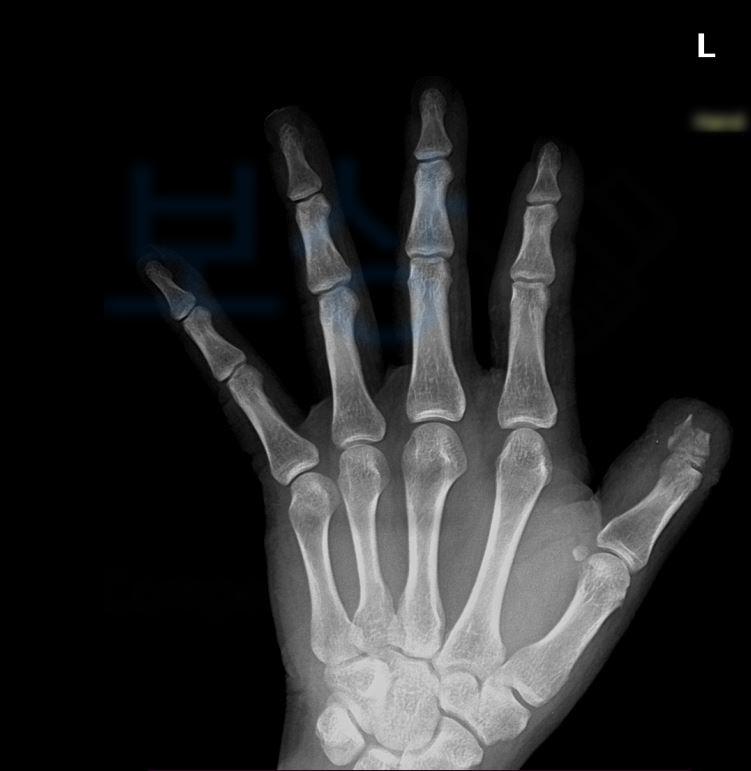

위 의무기록을 보시면 왼손의 첫째 손가락 즉 엄지손가락 뿐만 아니라

두 번째, 세 번째, 네 번째 까지… 통증을 호소하시고 골절되신 부분 확인됩니다… 내 보험증권에서 "후유장해” 항목을 찾아보세요. 의뢰인은 보험증권을 분석한 결과